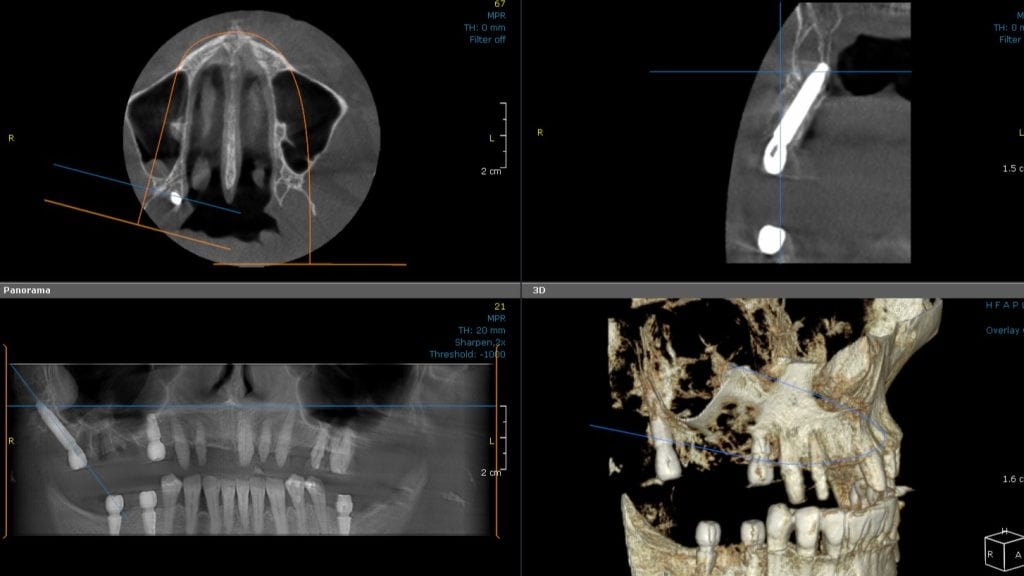

Examples of pterygoid implant placement